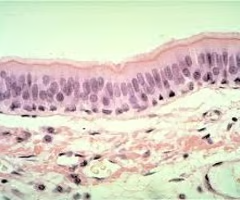

term image

basement membrane-between epithelium and underlying connective tissue